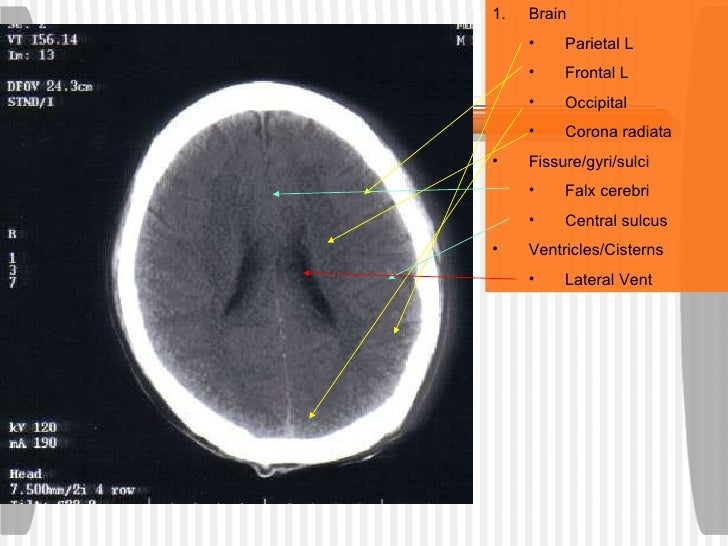

BASICS of CT Head

Basic approach to brain CT Dr. Muhammad Bin Zulfiqar